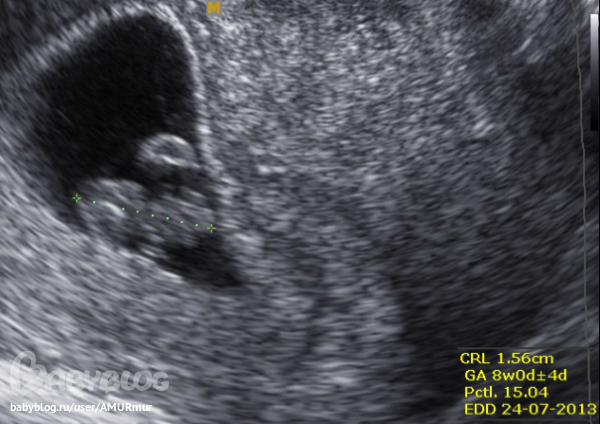

КТР 15,6 мм = 8 недель маточной беременности и... СЕРДЦЕБИЕНИЕ есть!!!! Рассматривать не стали и замер делать, решили не беспокоить малявочку, мне же главное было угрозу отмести и найти причину мазни! Всё... всёёёёёёёёёё! я спокойна как удав и счастлива! Все хорошо! А с гематомой я еще повоюю! Теперь я ее не боюсь.

А! еще забыла написать. Вот та лепешка, что над ножками моей малявочки - желточный мешочек, он, по словам узиста должен быть округлой формы, а у меня вытянутой... В общем, не опасность, просто какая-то странная особенность, главное - не маловат и не увеличен, остальное - не стоит внимания! На я уже умная, на УЗИ слушаю внимательно (в первое я пялилась в монитор и была как в тумане, голос узиста слышу, а что говорит - вот б вспомнить?!)))), вот и запомнилось.